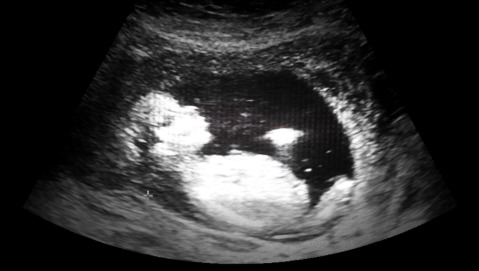

Come spiega il dottor Matteo Lambertini, oncologo presso l'IRCCS San Martino-IST di Genova, «uno degli effetti collaterali della chemioterapia è il danneggiamento del tessuto ovarico. Non è raro che le donne che si sottopongono alle cure vadano in menopausa precoce». Dal momento che l'incidenza del tumore al seno - ovvero il numero di nuovi casi - è in crescita anche nelle donne tra i trenta e i quarant'anni, è facilmente intuibile che in queste donne il desiderio di avere un figlio si scontri con la realtà di un ovaio che non può più generare ovociti maturi.

Per ovviare a questo problema negli ultimi anni si sono sviluppati degli approcci volti a cercare di preservare la fertilità. Uno di essi prevede il prelievo degli ovociti e il successivo congelamento in attesa di terminare la chemioterapia. Accanto a questo metodo utilizzato già da diverso tempo negli ultimi anni si è fatto largo un approccio che si basa sulla somministrazione, in concomitanza con la chemioterapia, di un analogo dell'ormone ipotalamico che stimola la secrezione di luteina (LHRHa). La sostanza in questione - ne avevamo già parlato in occasione del congresso mondiale di oncologia - è capace di mettere a riposo le ovaie preservandole da possibili danneggiamenti indotti dalla chemio. Un'opzione in più se si considera che in molti casi iniziare le terapie il prima possibile è di fondamentale importanza e non c'è tempo per il prelievo di tessuto ovarico.